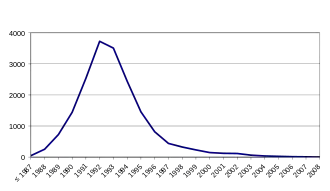

Four cases were reported globally in 2017, and the condition is considered to be nearly eradicated.[1] In the United Kingdom, from 1986 to 2015, more than 184,000 cattle were diagnosed with the peak of new cases occurring in 1993.[3] A few thousand additional cases have been reported in other regions of the world.[1] In addition, it is believed that several million cattle with the condition likely entered the food supply during the outbreak.[1]

The first confirmed instance in which an animal fell ill with the disease occurred in 1986 in the United Kingdom, and lab tests the following year indicated the presence of BSE; by November 1987, the British Ministry of Agriculture accepted it had a new disease on its hands.[66] Subsequently, 177 people (as of June 2014) contracted and died of a disease with similar neurological symptoms subsequently called (new) variant Creutzfeldt–Jakob disease (vCJD).[67][68] This is a separate disease from 'classical' Creutzfeldt–Jakob disease, which is not related to BSE and has been known about since the early 1900s. Three cases of vCJD occurred in people who had lived in or visited the UK – one each in the Republic of Ireland, Canada, and the US. Also, some concern existed about those who work with (and therefore inhale) cattle meat and bone meal, such as horticulturists, who use it as fertilizer. Up-to-date statistics on all types of CJD are published by the National Creutzfeldt–Jakob Disease Surveillance Unit in Edinburgh, Scotland.

For many of the vCJD patients, direct evidence exists that they had consumed tainted beef, and this is assumed to be the mechanism by which all affected individuals contracted it. Disease incidence also appears to correlate with slaughtering practices that led to the mixture of nervous system tissue with ground meat (mince) and other beef. An estimated 400,000 cattle infected with BSE entered the human food chain in the 1980s. Although the BSE epizootic was eventually brought under control by culling all suspect cattle populations, people are still being diagnosed with vCJD each year (though the number of new cases currently has dropped to fewer than five per year). This is attributed to the long incubation period for prion diseases, which is typically measured in years or decades. As a result, the full extent of the human vCJD outbreak is still not known.